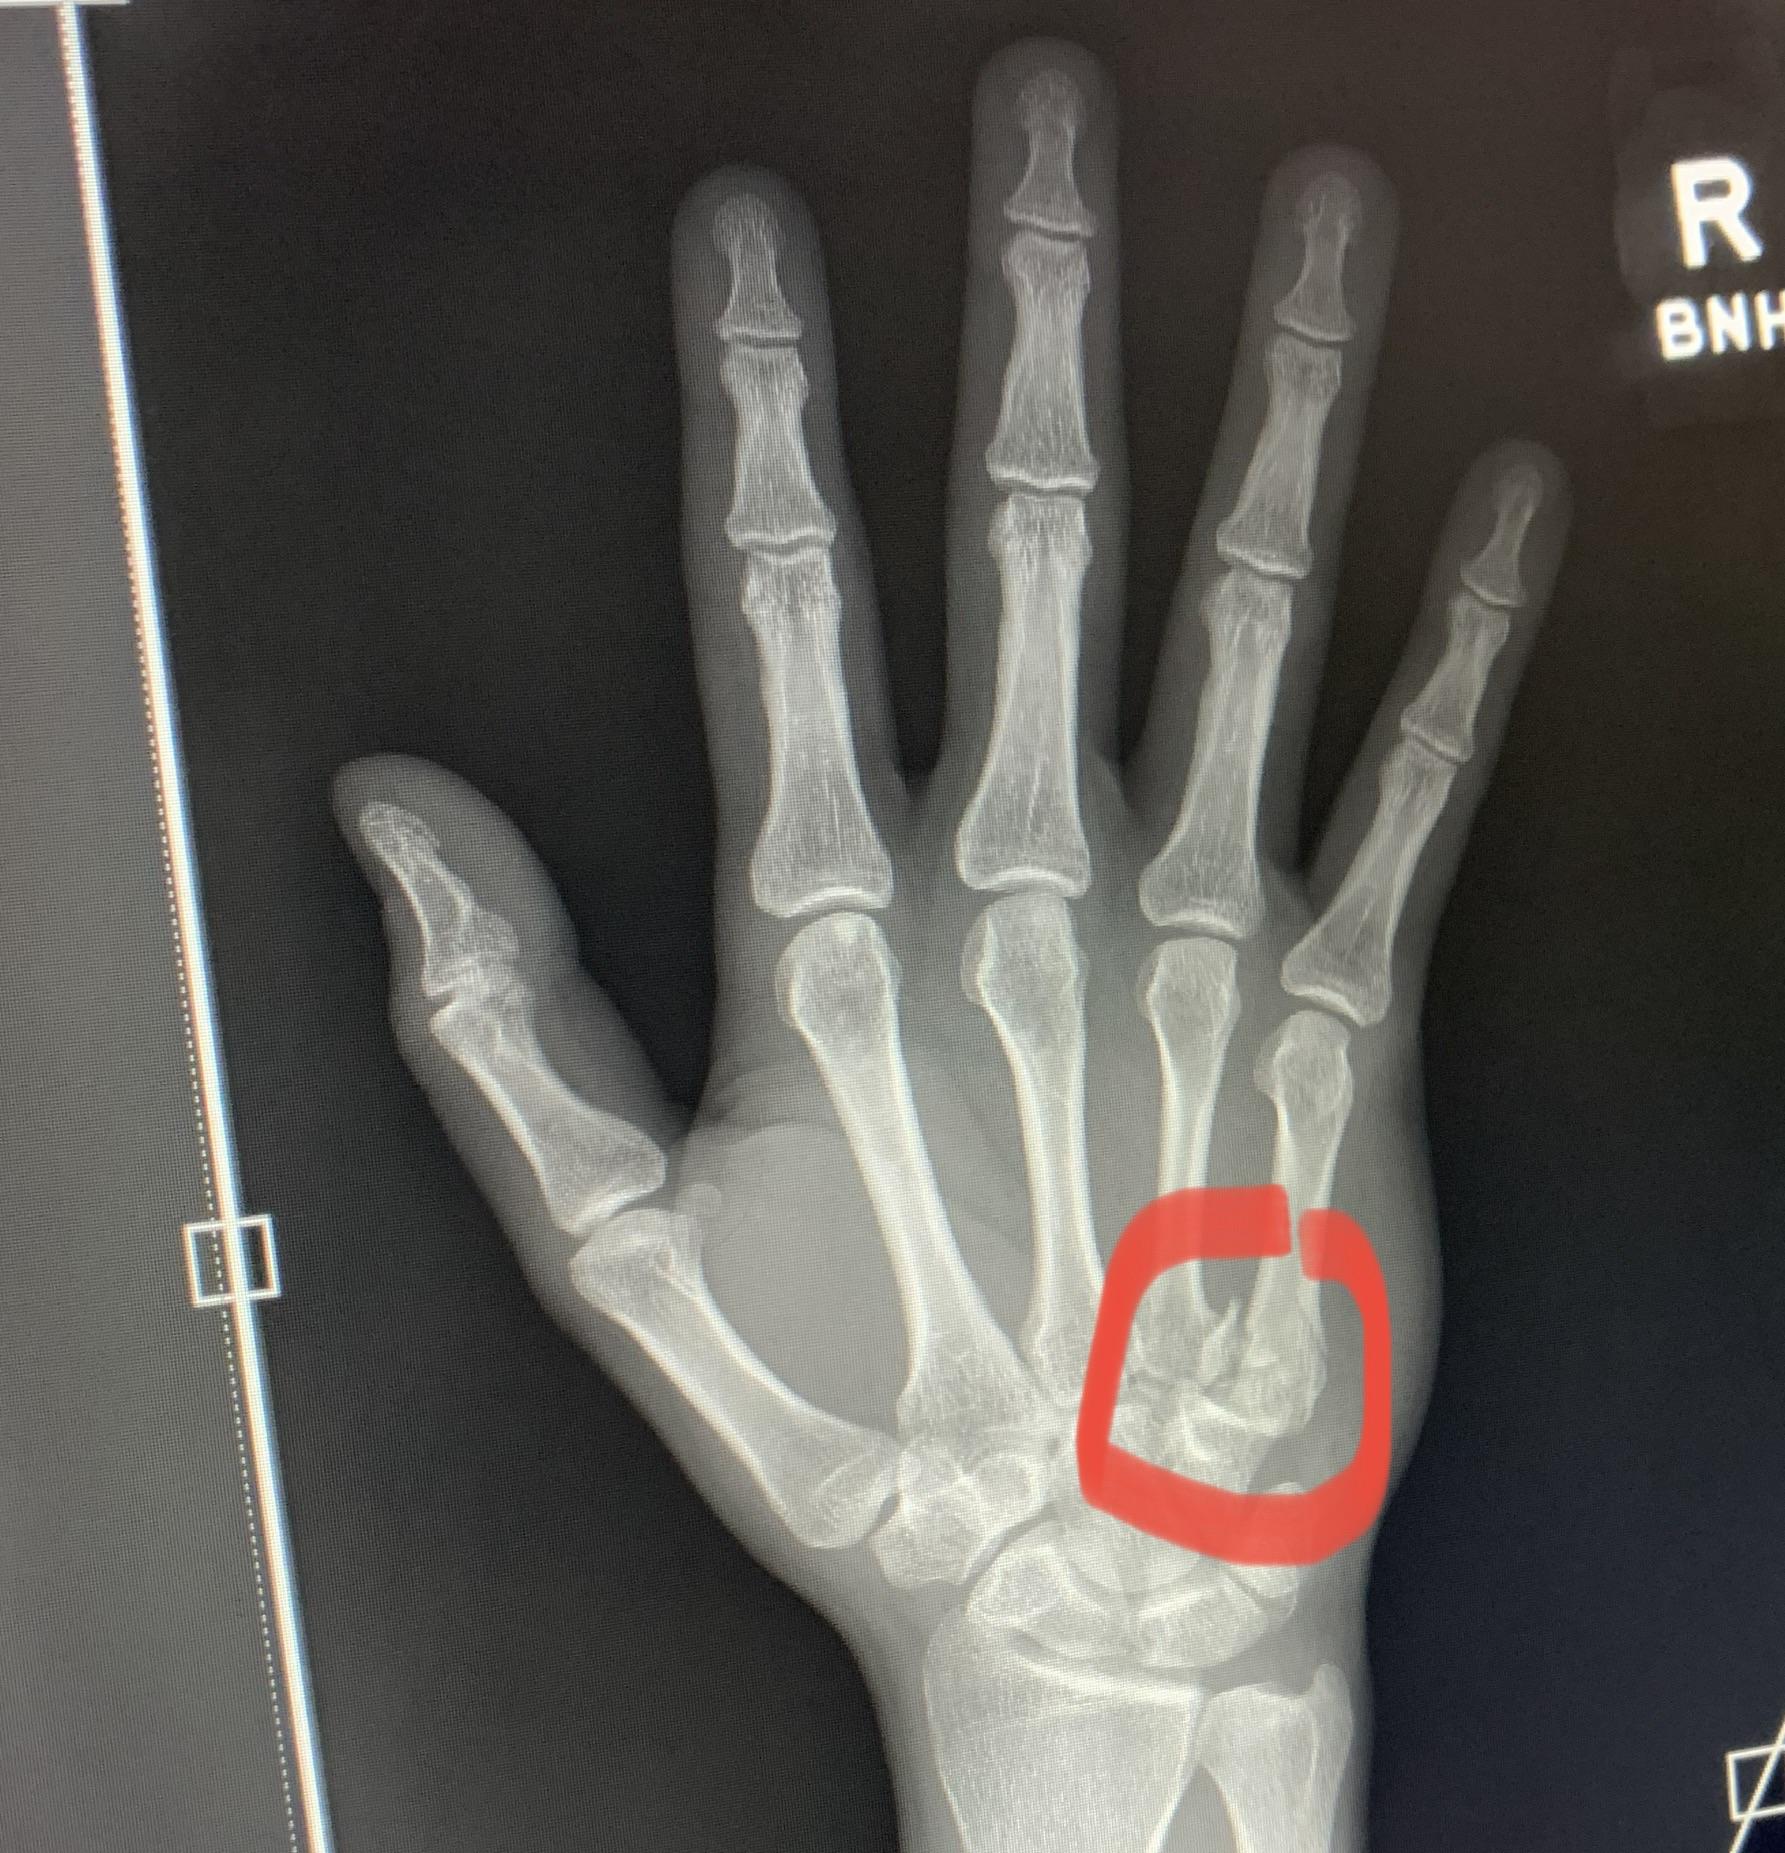

Boxer fracture. Radiograph shows a fracture of the fifth metacarpal Define Boxer's Fracture A boxer’s fracture is a fracture (broken bone) of the hand. More specifically, it is a fracture of the neck of the fifth metacarpal (a bone in the. A boxer's fracture is a break in a metacarpal bone that connects the ring finger or the little finger to the wrist. These are known as the fourth and. A boxer's fracture. Define Boxer's Fracture.